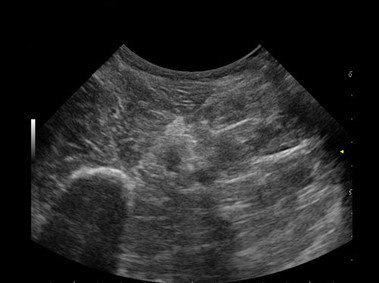

Das MyLab™One steht für das revolutionäre „Arm-held“ Hochleistungs-Ultraschallsystem mit 12”-Full-Touchscreen. Aufgrund seines geringen Gewichts und der Tragbarkeit kann es auch ohne Arbeitsfläche verwendet werden. Eine einzelne Person kann dieses Gerät aufgrund seiner einzigartigen Funktionen allein und selbstständig bedienen.

Das Ultraschallsystem MyLab™One zeigt exemplarisch den modernen Bedarf an Diagnosekapazitäten in verschiedenen Anwendungsbereichen: Radiologie, Kardiologie, Phlebologie, Frauenheilkunde, Orthopädie, Regionalanästhesie, Sportmedizin, Interventionell, Rheumatologie, Erste Hilfe, Notfallmedizin, Vaskuläre Reihenuntersuchungen, Allgemeinpraxis.

Der intuitive Touchscreen bietet dem Benutzer schnellen und einfachen Zugang zu allen Steuerungsfunktionen. Mit der beeindruckenden Bildqualität und einem kompakten Design wird MyLab™One zur idealen Ultraschalllösung am Point-of-Care.

Kompromisslos für den Point-of-Care: konzipiert für Ihre Umgebung

Die kompromisslose Ausrichtung auf den Point-of-Care bedeutet Fokus und Achtung auf spezifische Anwendungen, um bestimmte technologische Entwicklungen zu nutzen, die die wirksamsten Lösungen bewirken. Das MyLab™One kombiniert leistungsstarke Software mit einer Bedieneroberfläche, die speziell auf die Anwendung abgestimmt ist, und einem umfassenden Zubehör, das das MyLab™One zu einem perfekten System für alle klinischen Umgebungen und Workflows macht.

• Breites Bild mit hoher Qualität